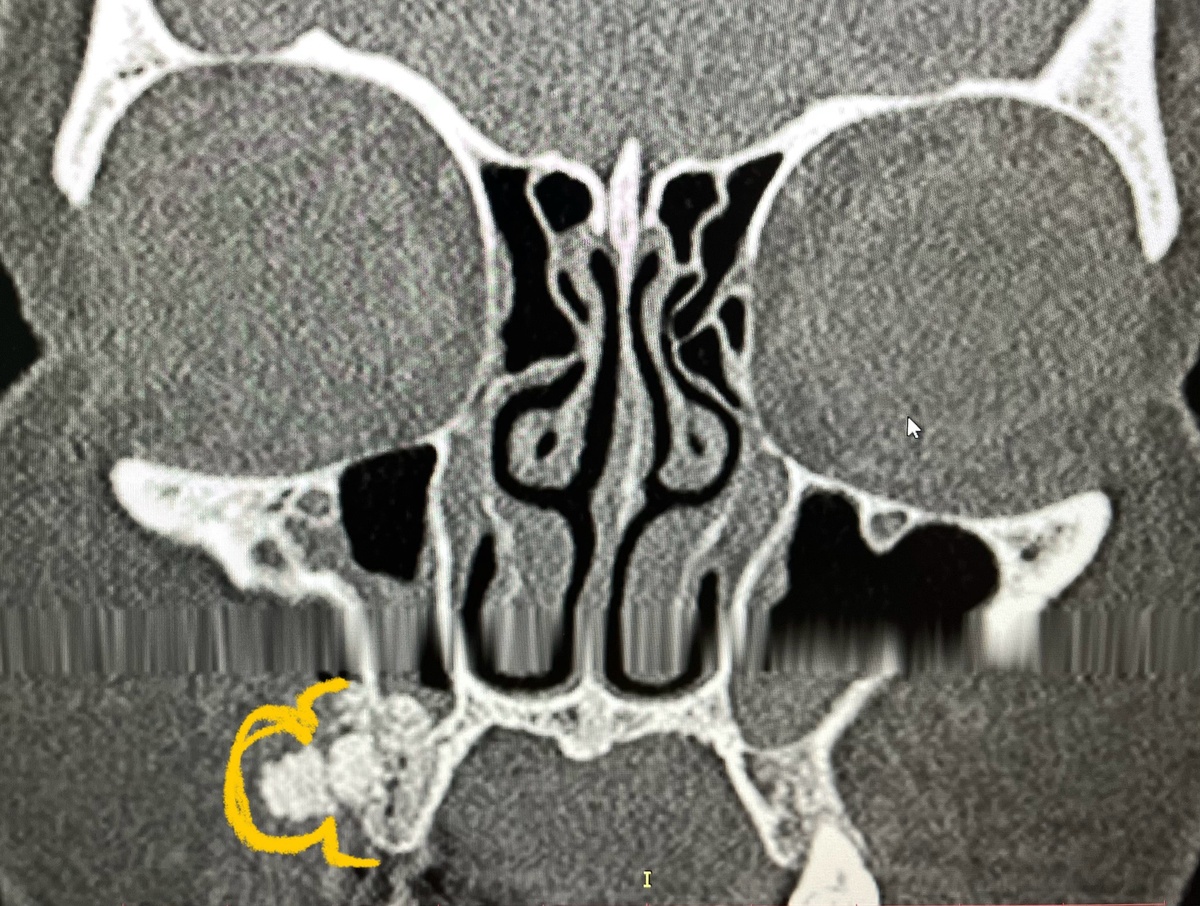

Дорогие читатели, спешу поделиться новым интересным клиническим случаем. Ко мне обратилась пациентка по поводу проведенной ей 2 месяца назад стоматологической операции под названием синус-лифтинг. Почему ко мне, ведь я ЛОР? Потому что это смежные области, и порой для осуществления следующих шагов (в данном случаем, установки импланта) нужно заглянуть немного дальше. Также на снимке пациентки обнаружилась ещё одна находка, о которой я сообщу в конце. Сначала небольшая справка, чтобы вы понимали, о чём речь: Синус-лифтинг представляет собой операцию по увеличению костной массы (и соответственно, толщины) верхней челюсти, с целью создания достаточной опоры для последующей установки зубных имплантатов. Операция может быть закрытой либо открытой. Проводится она следующим образом: в зоне имплантации делают отверстие, дно верхнечелюстной [гайморовой] пазухи смещают кверху, в полость вводят костнопластический материал и устанавливают защитную мембрану для фиксации материала и лучшего зажи

Синус-лифтинг. Выход материала в мягкие ткани. «Галя, у нас отмена!»